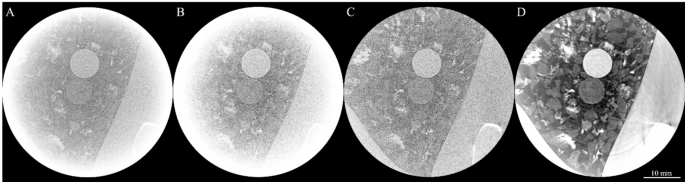

Correction of ROI-associated artefacts

The resultant CT slice reconstructions, following those phase retrieval and artefact-removal methods outlined above, were significantly improved compared to a standard filtered-back-projection (FBP) approach. Figure 3 shows the progression of the reconstructions from (A) a FBP reconstruction on the raw data, (B) ring artefacts removed, but cupping artefacts remaining, (C) with the cupping artefacts corrected, and (D) the final reconstruction with all artefacts corrected and phase retrieval applied. Note that the grey levels in D are adjusted to maximise contrast within the lung space, hence the bone is only saturated in the displayed image, not the data.

A visual representation of the reconstruction of the ROI CT scans containing three simulated spherical tumours at 50 keV and 7 m. (A) shows the raw data, (B) removal of ring artefacts (C) over padding applied to remove cupping and (D) the final reconstruction with ring removal, phase retrieval and over padding applied. The contrast is scaled differently for each panel to show relevant details.